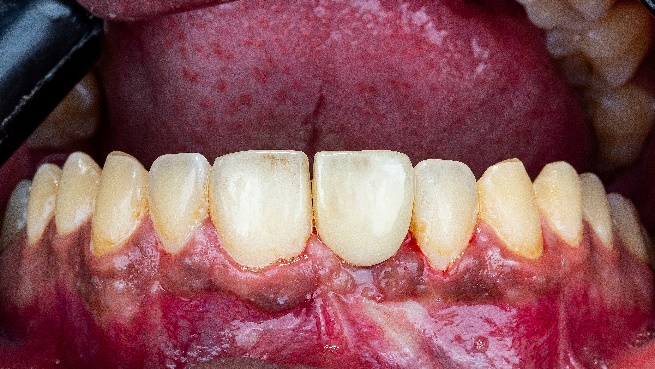

The patient, a 35-year-old male, sought treatment six months after losing his anterior tooth (21) due to trauma. Clinical examination revealed soft tissue depression in the edentulous area, while CBCT imaging showed insufficient horizontal bone width (<4mm) in the region, with normal vertical bone height, adjacent teeth, and occlusal relationships, the patient has high aesthetic demands. (Fig2,3,4,5)